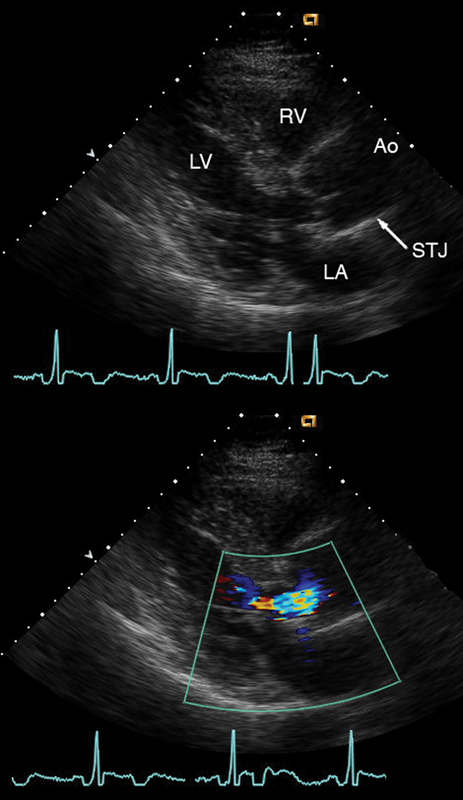

فحوصات تشخيصية لبعض امراض القلب والشرايين التاجية